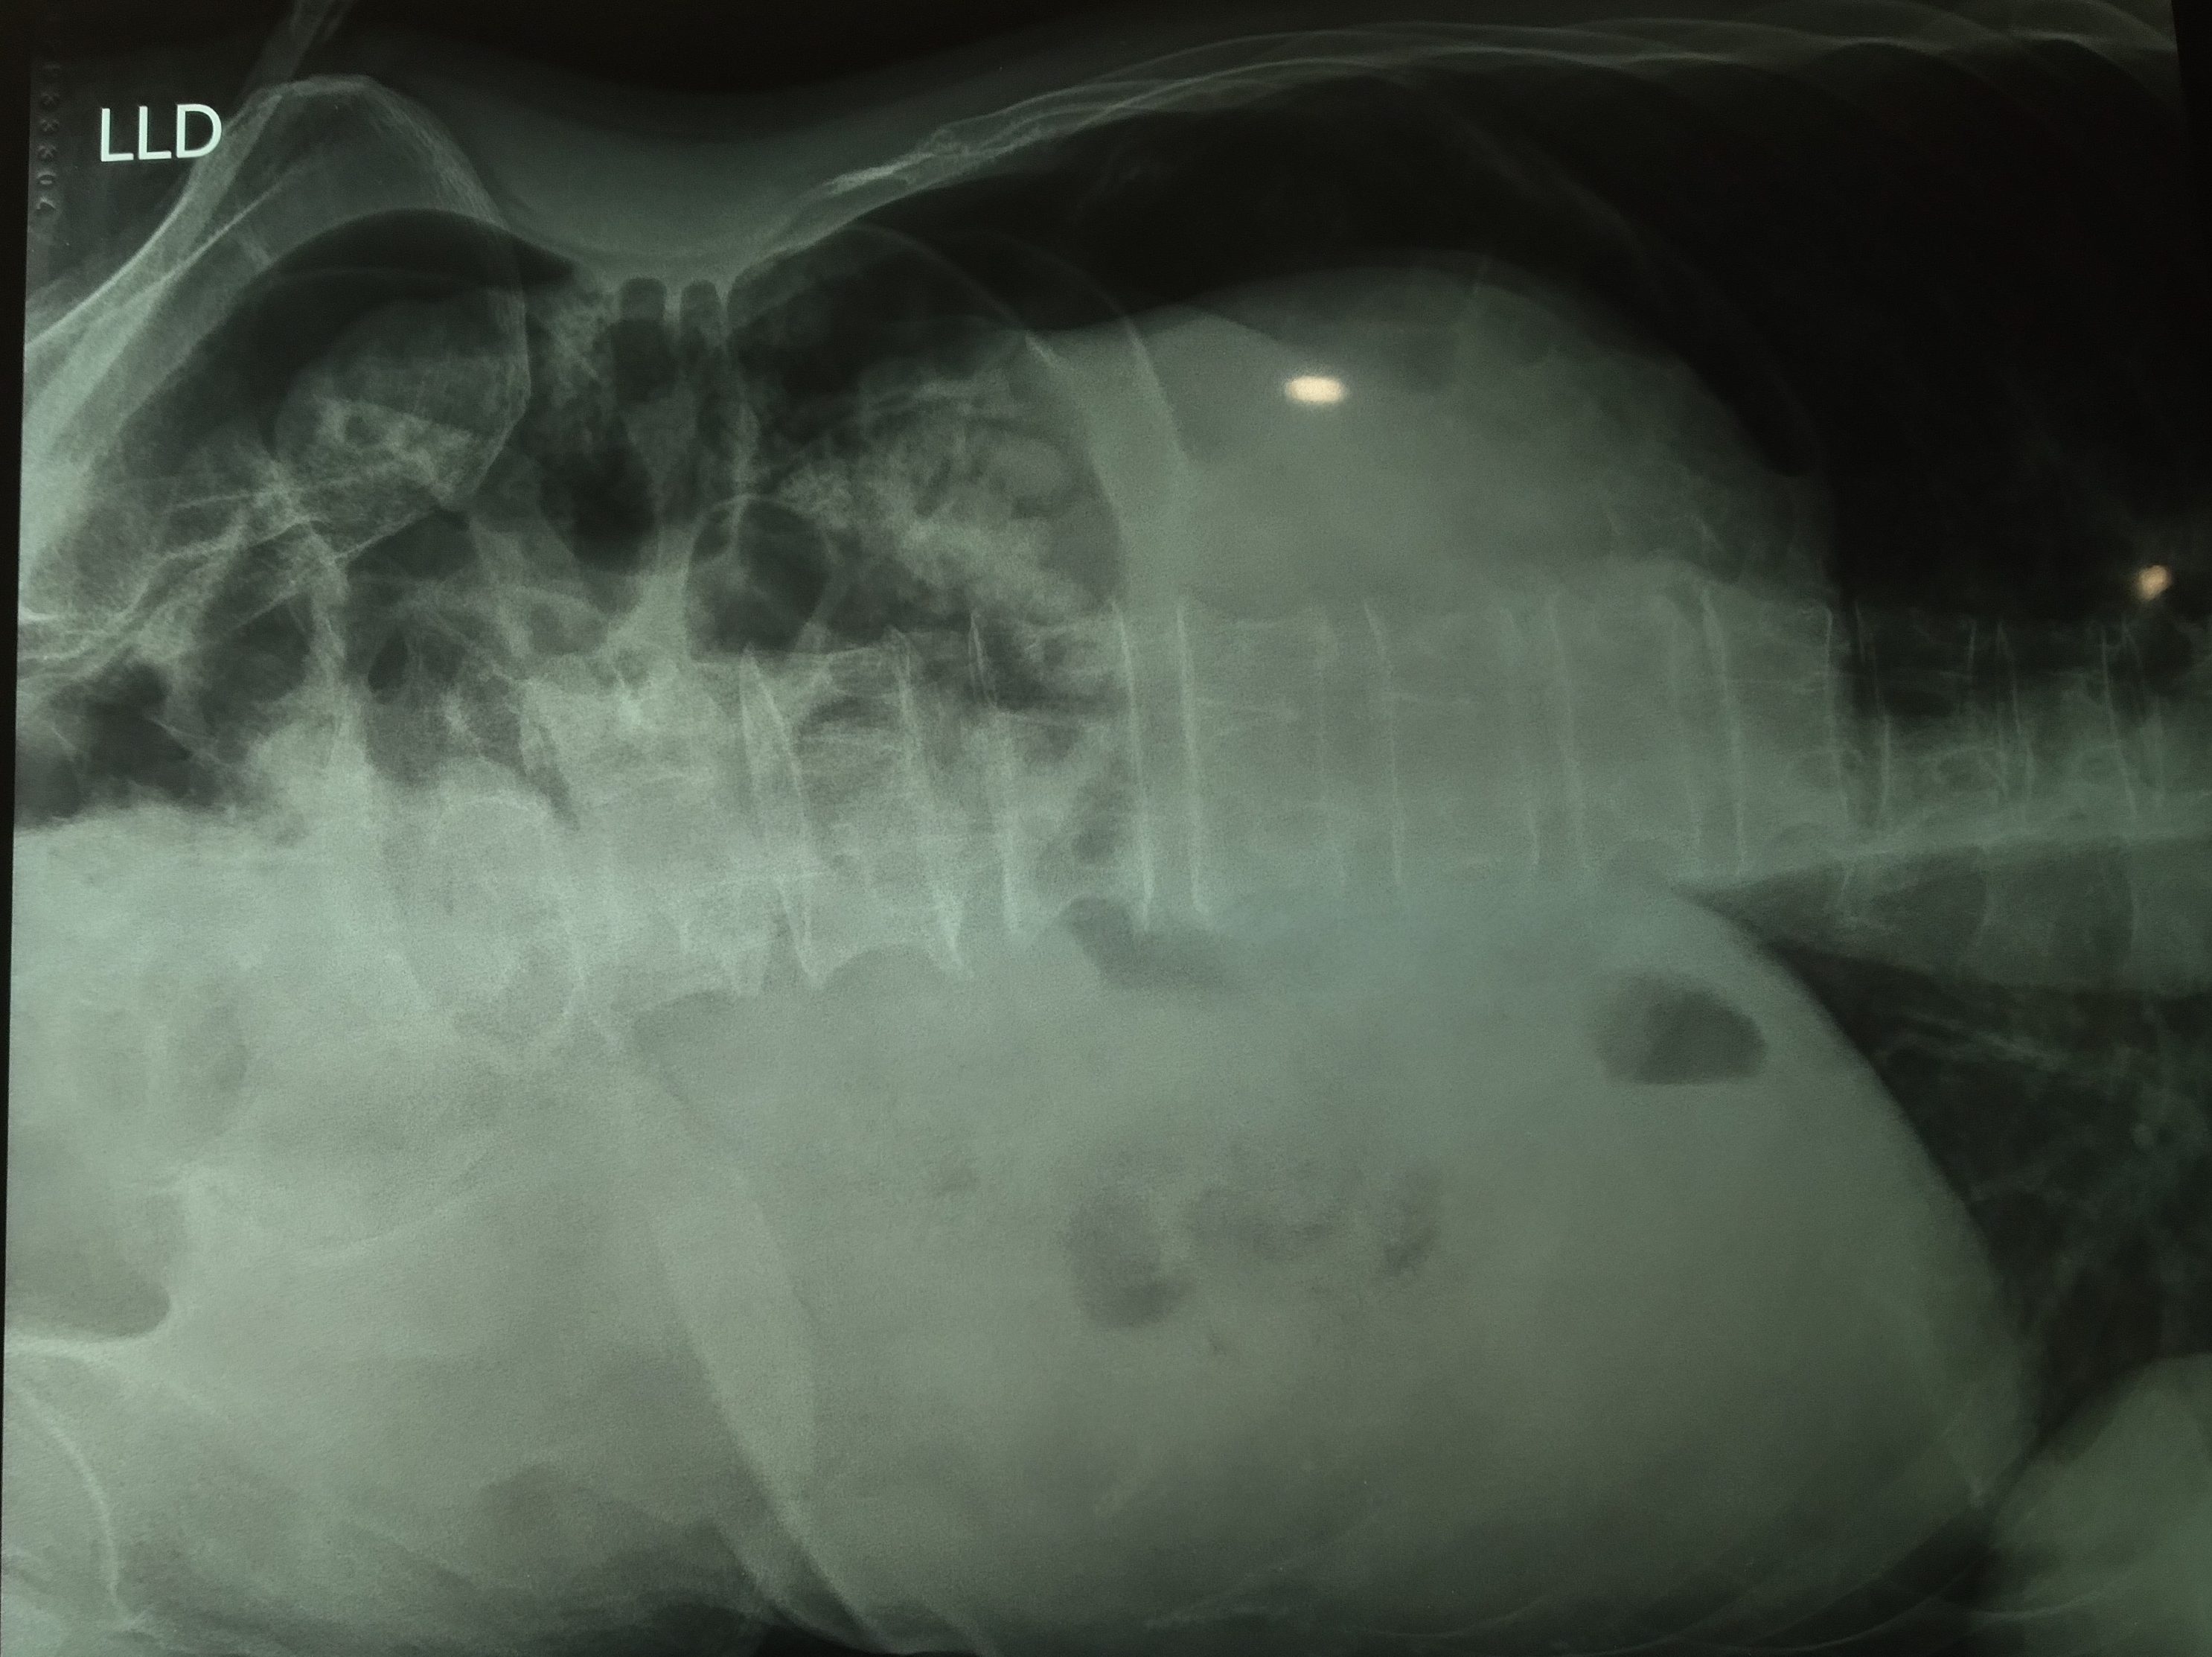

Gambar pembagian uveitis secara anatomi2